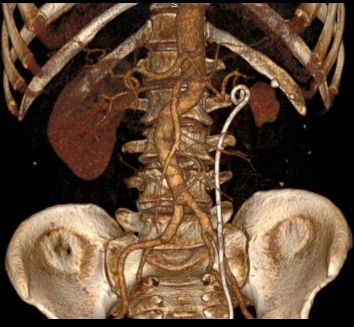

• Phình động mạch tạng (Visceral Artery Aneurysms - VAA)

• Phình động mạch thận (Renal Artery Aneurysm - RAA)

• Giả phình động mạch thận (Renal Artery Pseudoaneurysm)